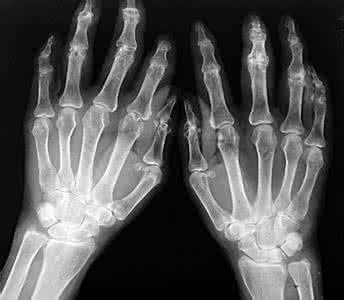

• 成都风湿病医院排名?类风湿病手指关节轻微变形还能恢复吗?

修复的可能性比较小,目前治疗类风湿没有比较好的方法,大都采用 ...